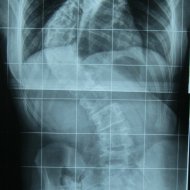

Farklı tipte skolyozu olan hastaların ameliyat öncesi ve sonrası fotoları: